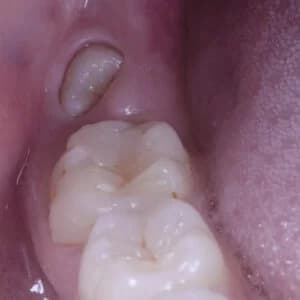

¿Qué son las Muelas del juicio?

Son los últimos molares en aparecer y lo hacen en edad adulta, entre los 17 y 20 años. Allí surge el problema: con poco espacio para albergarlas, comienzan los síntomas.

Pueden nacer torcidas, afectar el resto de la dentadura, causar maloclusión, infección y otros problemas. Si no están en la posición ideal, recomendamos extraerlas cuanto antes.